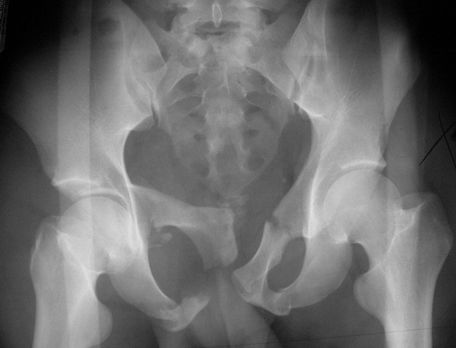

正常骨盆正位片

疼痛科怎么理疗疼痛科医生、康复理疗科医生、针刀针灸医生应掌握的常见骨科疾病X光片_https://www.jmylbn.com_新闻资讯_第47张